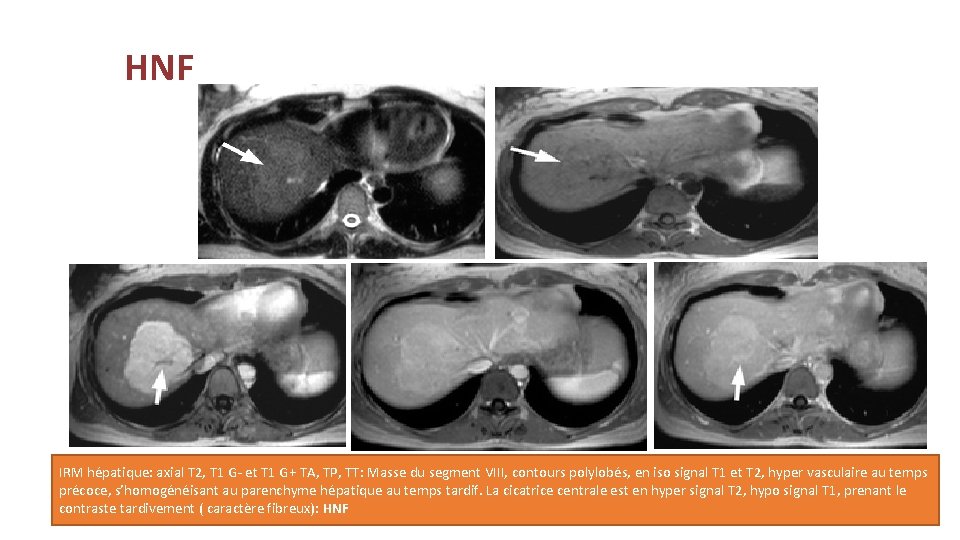

HNF IRM hépatique: axial T 2, T 1 G- et T 1 G+ TA, TP, TT: Masse du segment VIII, contours polylobés, en iso signal T 1 et T 2, hyper vasculaire au temps précoce, s’homogénéisant au parenchyme hépatique au temps tardif. La cicatrice centrale est en hyper signal T 2, hypo signal T 1, prenant le contraste tardivement ( caractère fibreux): HNF

Bénignes : Hyperplasie nodulaire focale: • La seconde tumeur bénigne par ordre de fréquence après l’hémangiome, souvent de découverte fortuite. • Quasiment toujours asymptomatique et toujours bénigne. • Echographie: Iso-échogène, hypoéchogène ou hyperéchogène de contours lobulés, ayant une cicatrice centrale. • Scanner: • Sur l’acquisition non injectée iso-dense ou hypodense. • Sur les acquisitions injectées: au temps artériel prise de contraste intense sauf la zone centrale, aux temps portal et tardif elle redevient iso-dense au parenchyme hépatique avec l’élément central qui se rehausse au temps tardif.